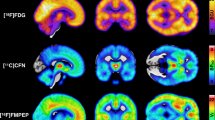

Maternal obesity during pregnancy increases the risk for offspring obesity, in part through effects on the developing brain. Previous research has shown that perinatal consumption of highly palatable foods by the mother can influence the development of offspring taste preferences and alter gene expression within the central nervous system (CNS) reward system. Opioids stimulate consumption of both fats and carbohydrates, and overconsumption of these energy dense foods increases the risk for obesity. What has remained unclear is whether this risk can be transmitted to the offspring before gestation or if it is wholly the gestational exposure that affects offspring brain development. Utilizing an embryo transfer experimental design, 2-cell embryos were obtained from obese or control dams, and transferred to obese or control gestational carriers. Expression of the mu-opioid receptor (MOR), preproenkephalin (PENK), and the dopamine transporter was evaluated in the hypothalamus and reward circuitry (ventral tegmental area, prefrontal cortex, and nucleus accumbens) in adult and late embryonic brains. Obesity before pregnancy altered expression levels of both MOR and PENK, with males relatively more affected than females. These data are the first to demonstrate that obesity at conception, in addition to during gestation, can program the brain reward system.